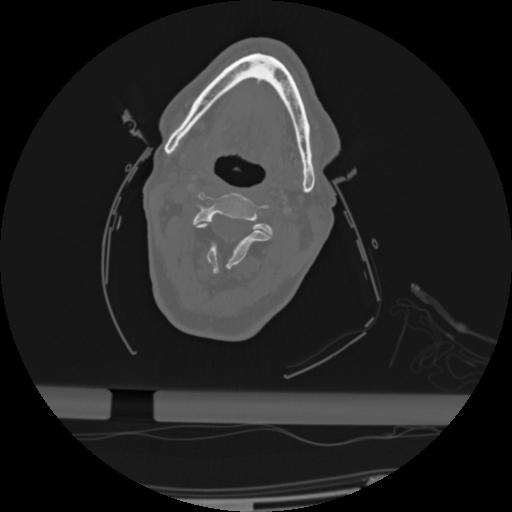

22 ANGIO,CE,Vol,0.5,ANGIO,,